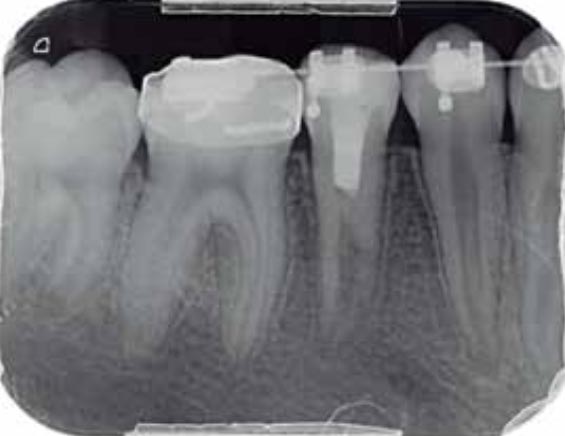

Imágenes: Reendodoncia en un molar inferior derecho